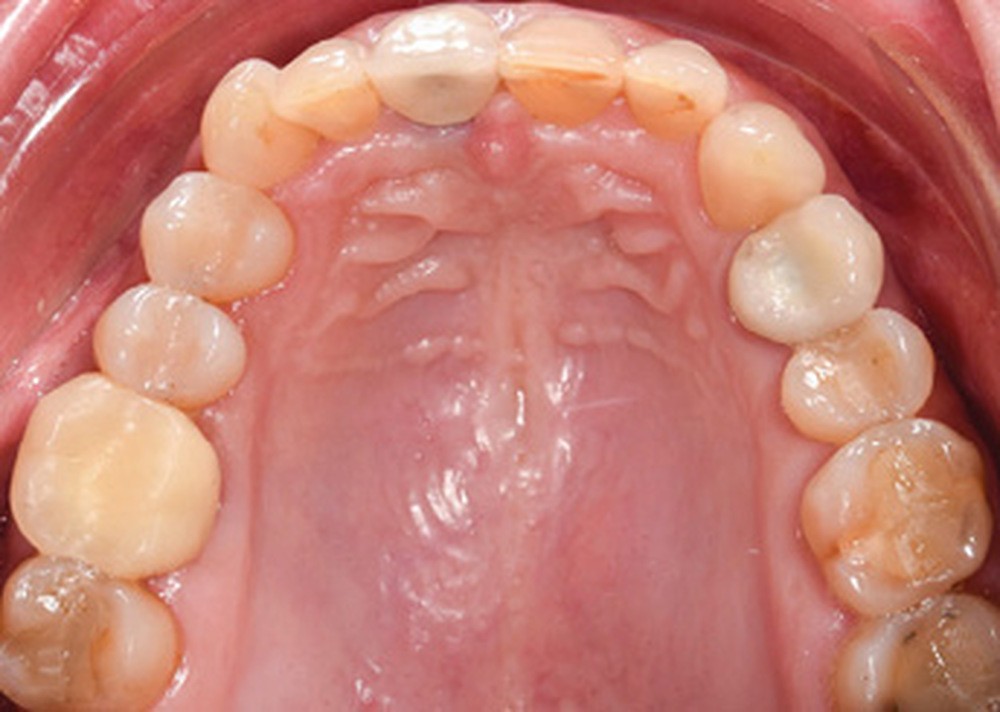

Examen endobuccal (fig. 2a-e)

L’arcade maxillaire est asymétrique et parabolique. Elle présente une mésio-position du secteur 1. On note des rotations mésio-vestibulaire de 13 et disto-vestibulaire de 23 et une palato-version incisive. Les restaurations prothétiques sur 11, 16 et 24 semblent à refaire. L’arcade mandibulaire est asymétrique et parabolique avec une couronne sur implant en 36.

Dans la dimension transversale, on constate une endoalvéolie maxillaire. Dans la dimension sagittale, on observe une classe II plus importante à droite où elle est complète de 5 mm. Le surplomb est absent et la supraclusion totale (6 mm) par supra-alvéolie mandibulaire.